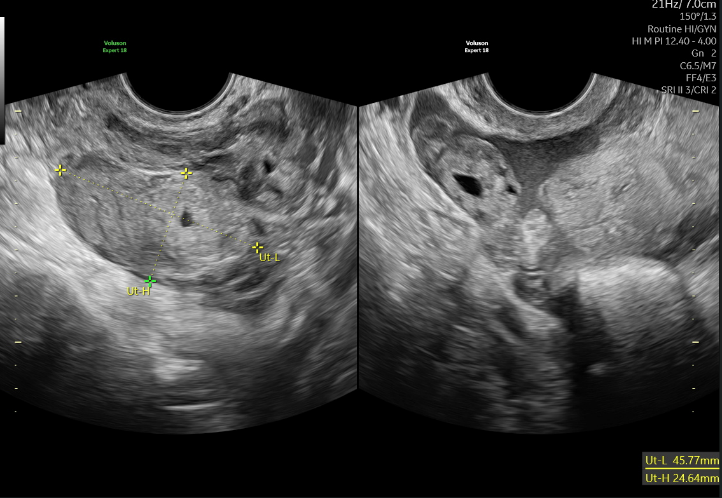

Hình 1. Hình ảnh siêu âm tử cung phần phụ

Chẩn đoán: Thai ngoài tử cung trái đã vỡ (một tình huống có thể gây xuất huyết nặng và nguy hiểm tính mạng nếu không được xử trí kịp thời).